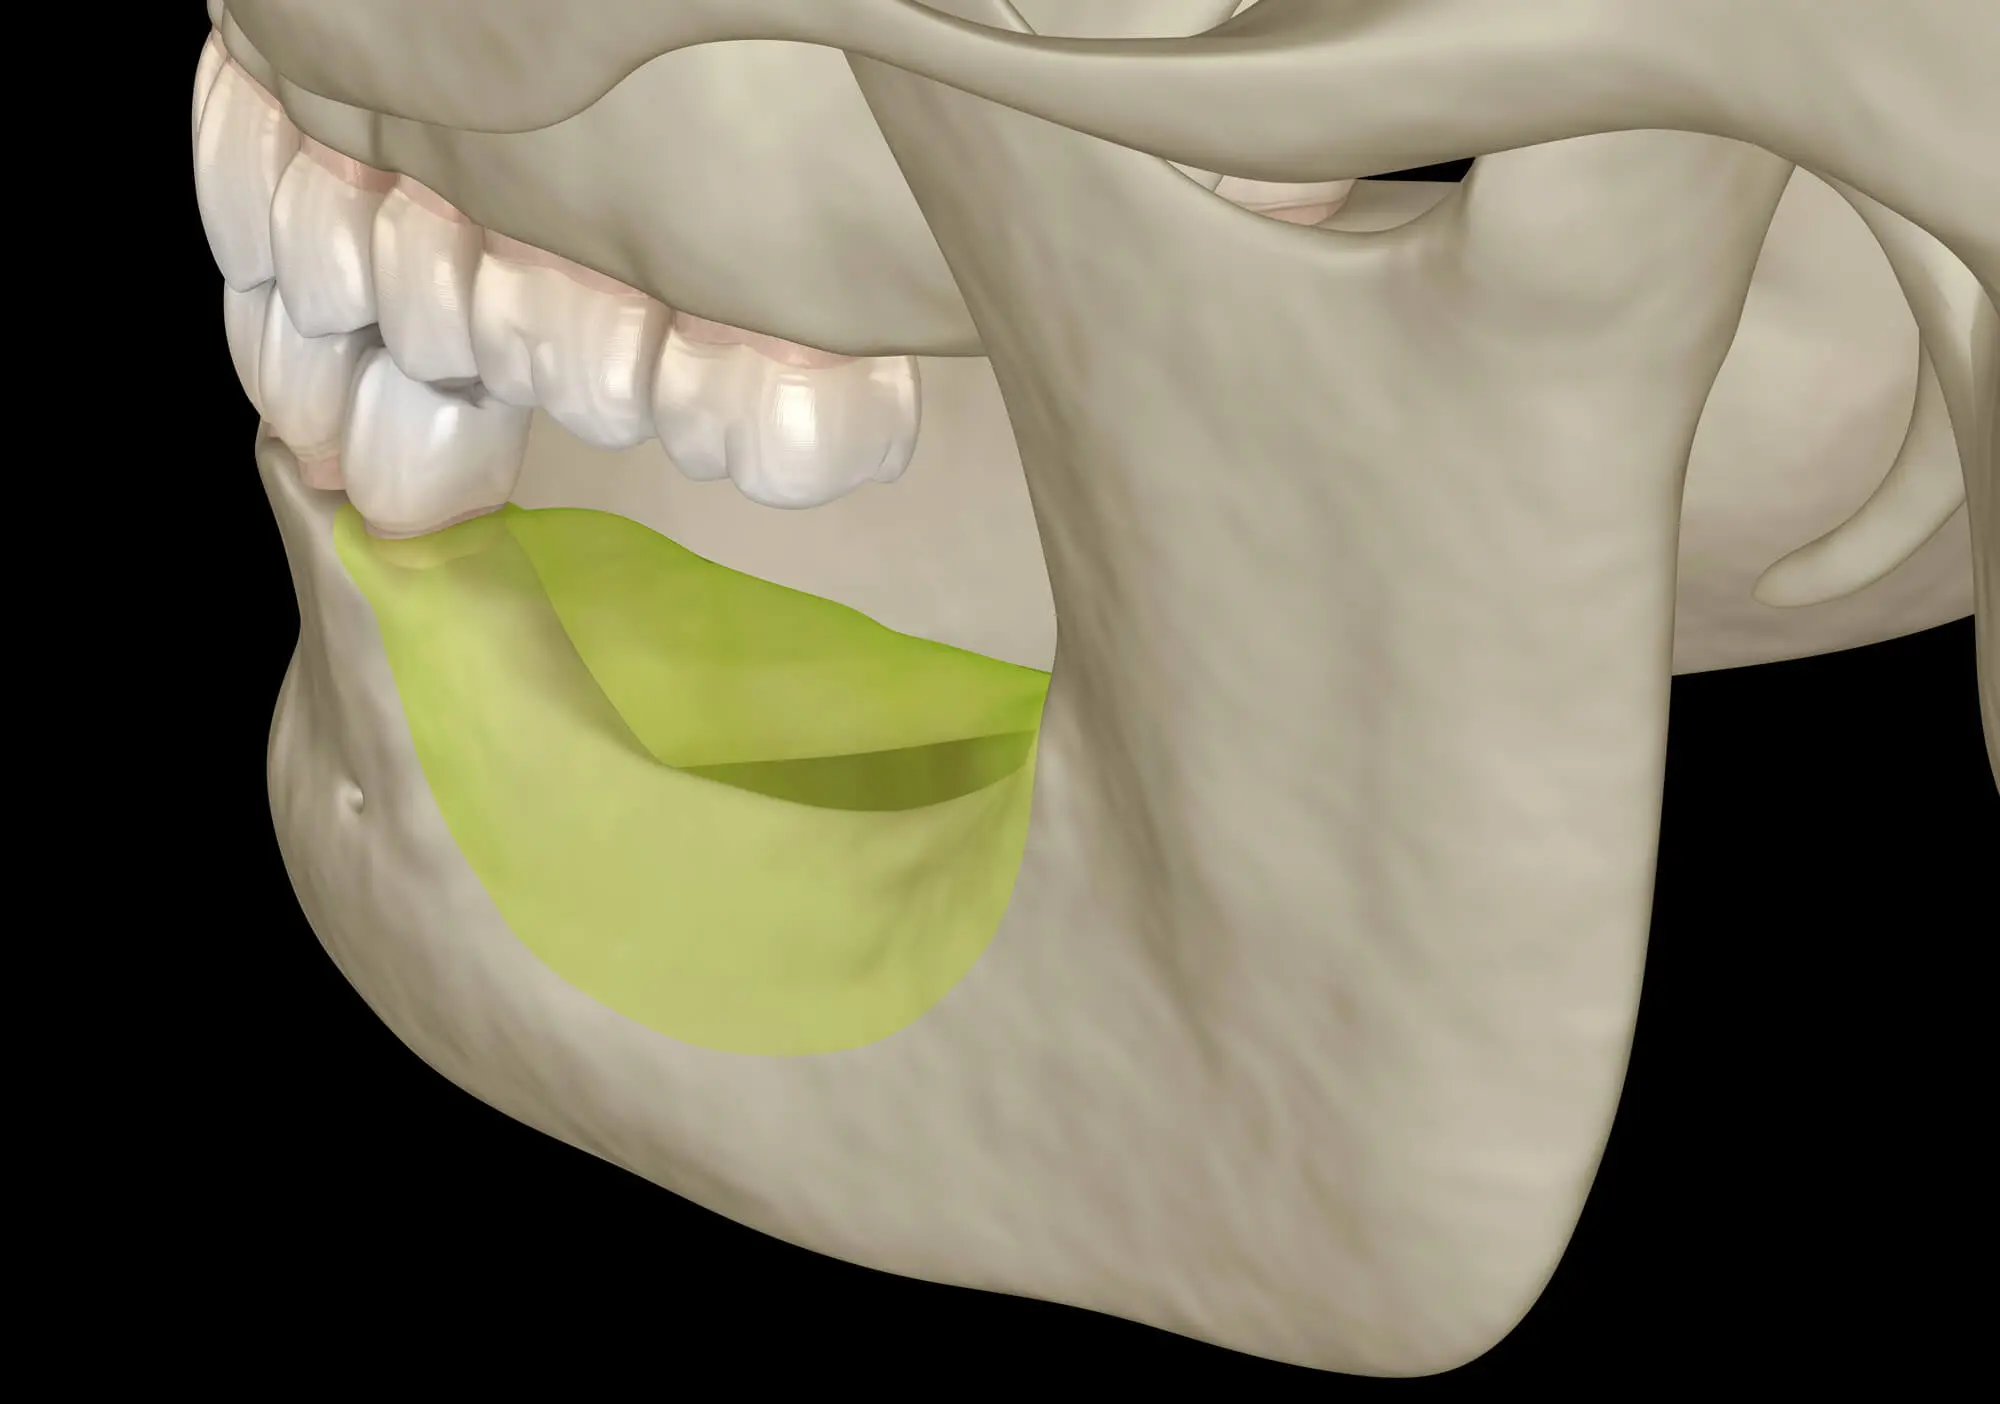

1. Your Jawbone Starts to Shrink

One of the most serious consequences of tooth loss is bone resorption, a process in which your jawbone begins to break down in the area where a tooth was lost. This happens because your teeth help stimulate your jawbone and keep it healthy, both from the blood vessels that go into your tooth, and the pressure provided by chewing that helps keep your bone strong.

Without that stimulation, the jawbone begins to break down the unused bone, causing degenerative changes.

Bone loss begins within the first few months after tooth loss, and once it starts, it’s difficult to reverse. Over time, this can weaken your bite, alter your facial structure, and complicate future tooth replacement options.